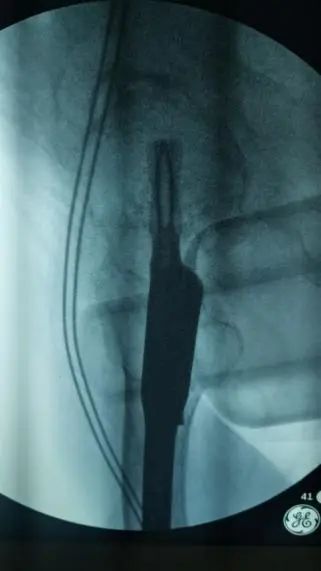

骨科团队迅速评估病情,认为手术治疗是让老人重新站起来的唯一希望,也是降低长期卧床并发症风险的最佳选择。在科主任李忠教授带领下,唐炼副主任医师团队反复研究影像资料,精心设计创伤小、固定可靠的手术方案——微创闭合复位股骨近端防旋髓内钉(PFNA)内固定术。手术仅用时30分钟顺利完成。